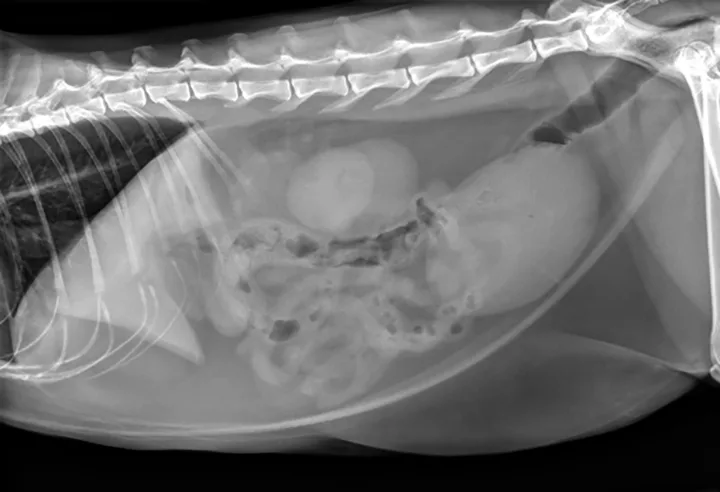

Figure 1. The urinary bladder appears large and there is bilateral renomegaly in this right lateral view; dystrophic mineralization is present in the right kidney.

At initial examination, Ivan was alert and responsive with heart rate, respiratory rate, and temperature within normal limits. He was estimated to be 5% dehydrated and had a large, firm, nonexpressible bladder. He was sedated with 0.015 mg/kg IV of buprenorphine, 0.2 mg/kg IV of midazolam, and administered a total of 2.5 mL of propofol IV for urinary catheter placement. A 5-French red rubber catheter was placed with slight resistance and maintained in place with butterfly tape and stay sutures. A CBC, serum chemistry panel, and plain abdominal radiographs (Figure 1) were performed.